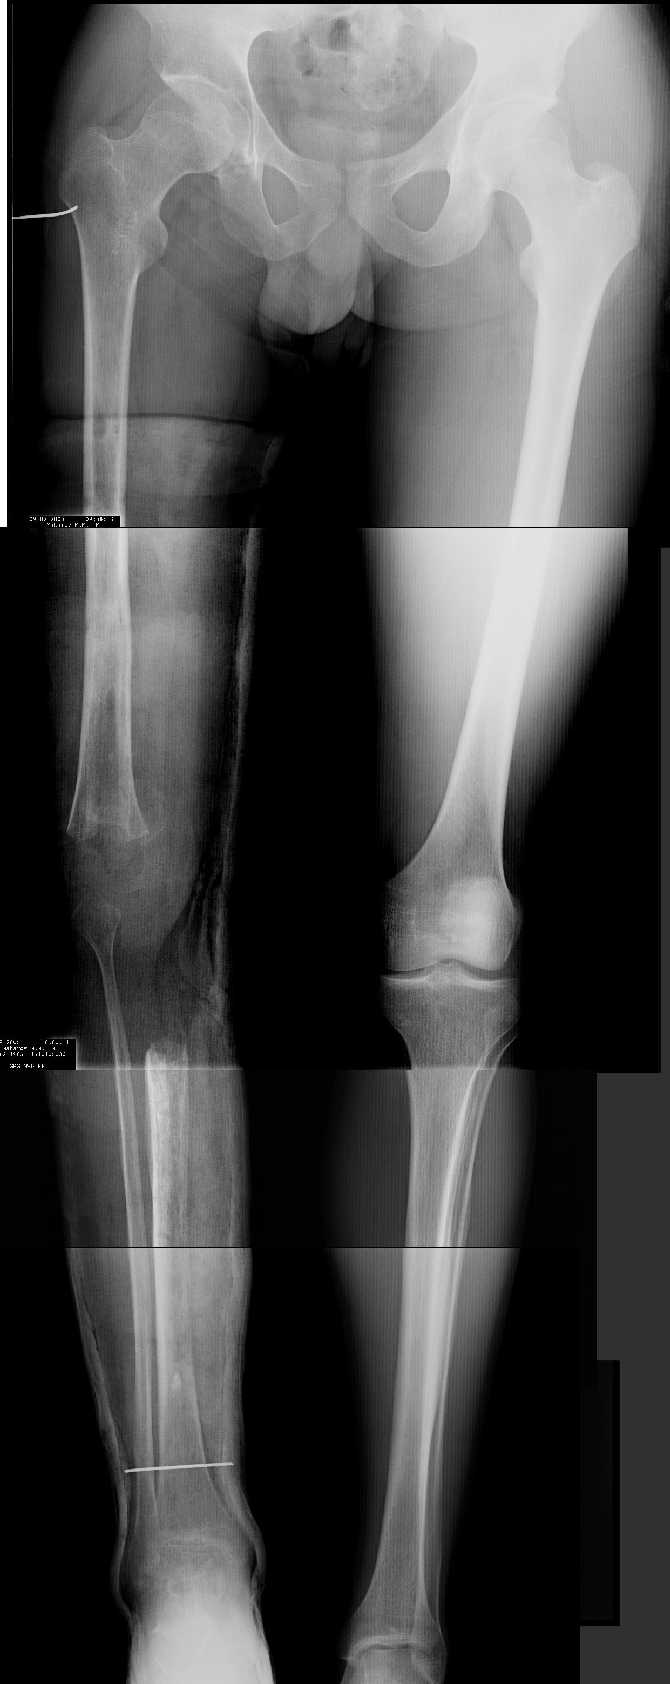

AV> многооскольчатый перелом правой бедреннойљ кости на границе

AV> средней и нижней трети со смещением,

AV> В настоящее время стойкая разгибательная контрактура правого

AV> коленного сустава (сгибание 105-110 гр., разгибание 160-165 гр.),

AV> варусная деформация, болевой синдром.

имеется S-образная деформация бедра на фоне "многооскольчатого

перелома правой бедреннойљ кости на границе средней и нижней трети со смещением"

(хотя "длинные" снимки конечно же не помешали бы...)

AVM> имеется S-образная деформация бедра на фоне "многооскольчатого

AVM> перелома правой бедреннойљ кости на границе средней и нижней трети со смещением"

На представленных снимках эта деформация как раз и не представлена.

1. Иллюстрации - во вложении.

Два бедра после эндопротезирования.

Авторы операции долго думали почему больная хромает.

Сдклали снимок - одна нога короче почти на 3 см.